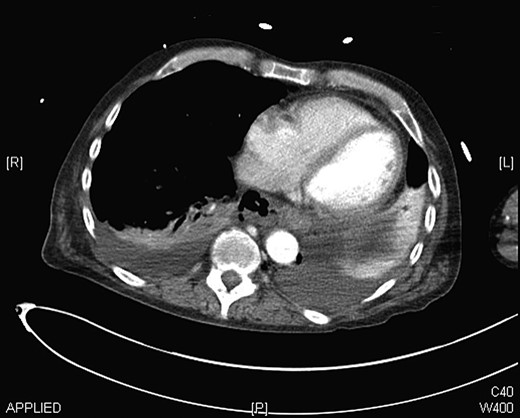

On admission, he had a Glasgow Coma Scale of 3 requiring aggressive resuscitation in the Intensive Care Unit (ICU). Contrast computed tomography (CT) chest showed mediastinitis, bilateral pleural effusions and free air around the distal posterior oesophagus (Fig. 1). A gastrograffin swallow confirmed an oesophageal perforation. He was transferred to the local specialist Upper Gastro-Intestinal Unit for further management.

CT chest showing mediastinitis, bilateral pleural effusions and free air around the distal oesophagus.